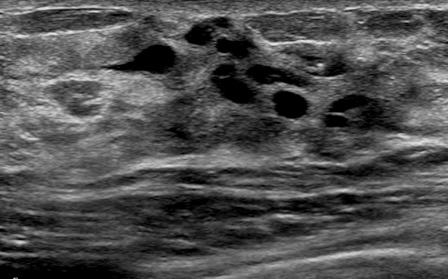

The target dataset was developed from 35 breast ultrasound scans that were segmented by an image-processing expert with extensive experience in breast lesion segmentation (the second author). The images, collected from the Web, are of different dimensions, ranging from to pixels (Figure 3, images resized for sake of illustration). These are the same images used to introduce EFIS originally [1].

Ultrasound images are generally difficult to segment, primarily due to the presence of speckle noise and low level of local contrast. It should be noted that the segmentation of ultrasound actually does require a complete processing chain, (including proper preprocessing and post-processing steps). However, the purpose of using these images was solely to demonstrate that the accuracy of the segmentation can be increased with the application of SC-EFIS.